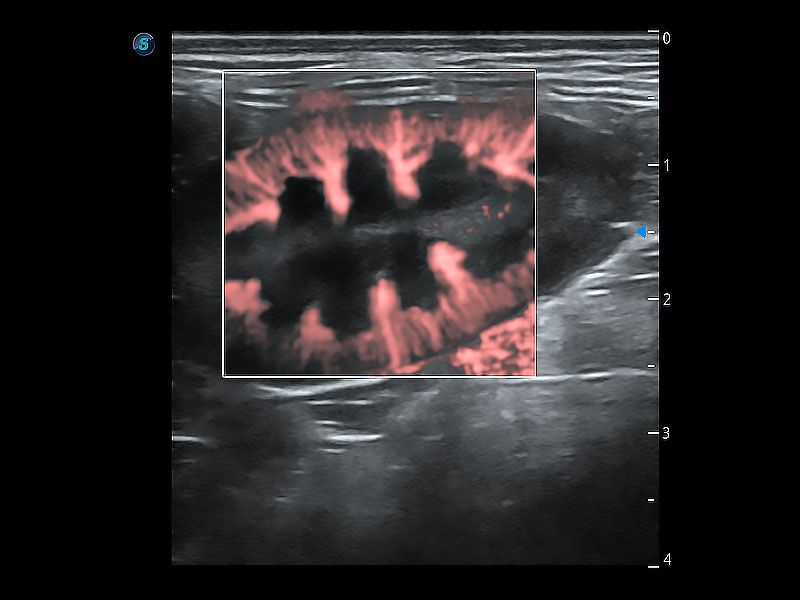

(犬)肠道

(犬)肾脏显微血流